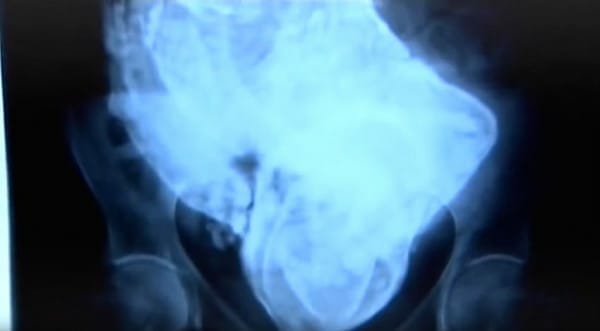

Fenomenet lithopedion är extremt ovanligt och innebär att ett större foster avlider utanför livmodern, ett så kallat utomkvedshavandeskap. Fostret blir kalcifierat för att skydda modern från förruttnelsen.

Fostret hade utvecklats utanför livmodern och blev sedan en främmande kropp för moderns immunsystem. Därför bildade kroppen ett skal av calcium runt det – varför fenomenet kallas ”stenbebis” eller ”stone baby” på engelska. Skalet hade blivit större och starkare med åren, för att skydda kvinnan från infektioner.

Zahra är den kvinnan i världen som ska ha haft kvar fostret under längst tid i kroppen, 46 år. Hon genomgick en väldigt svår operation, och läkarna trodde att hon kunde förlora mycket blod. Men operationen lyckades och Zahra ”födde” stenbebisen efter alla år.